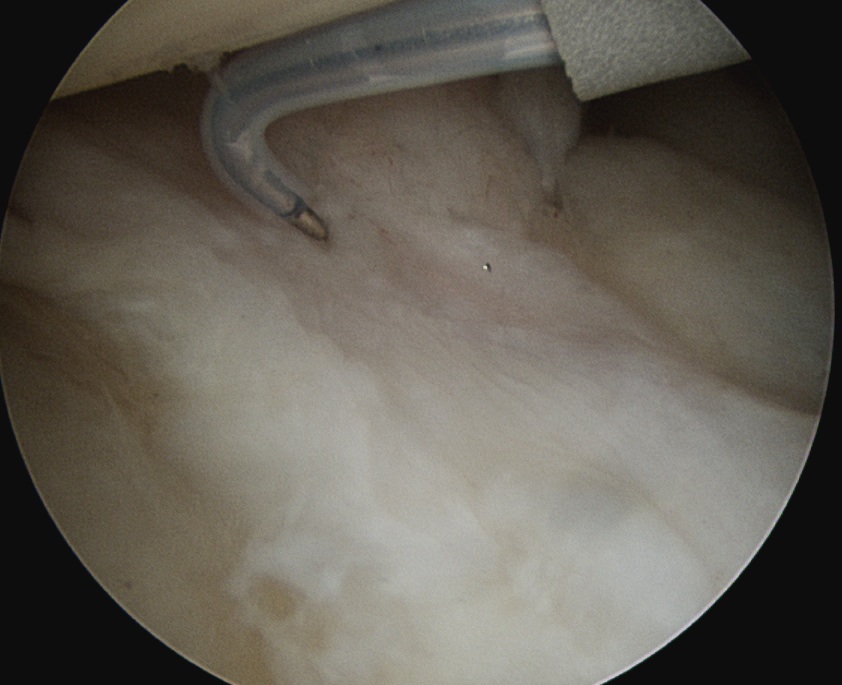

Rotator interval release

Release anterior IGHL

Release posterior IGHL